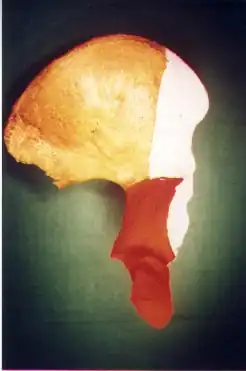

Both column fracture showing floating weight bearing dome

Both column fracture showing floating weight bearing dome -